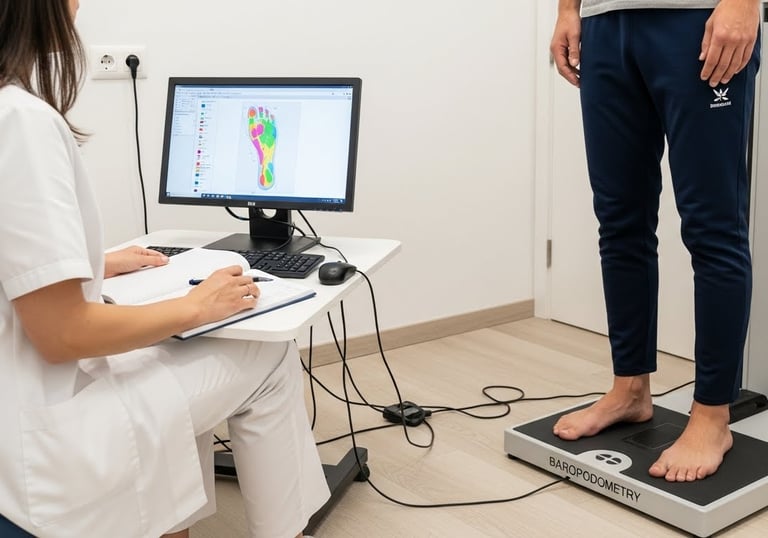

Baropodometria computadorizada